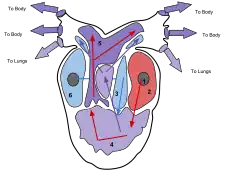

O coração humano divide-se em quatro cavidades. Na parte superior situam-se as aurículas direita e esquerda e, na parte inferior, os ventrículos direito e esquerdo.[4][5] É comum designar o conjunto da aurícula e do ventrículo direitos por "coração direito" e o conjunto equivalente do lado esquerdo por "coração esquerdo".[6] Num coração saudável, as válvulas cardíacas fazem com que o sangue dentro do coração flua em sentido único, impedindo o seu refluxo.[3] O coração é envolvido pelo pericárdio, uma membrana protetora em forma de saco que contém uma pequena quantidade de líquido. A parede do coração é constituída por três camadas: o epicárdio, o miocárdio e o endocárdio.[7] O coração dos restantes mamíferos e das aves apresenta igualmente quatro cavidades.[4] O coração dos peixes apresenta apenas duas cavidades, uma aurícula e um ventrículo, enquanto o dos répteis apresenta três cavidades.[5]

O coração direito irriga a circulação pulmonar. A aurícula direita recebe o sangue venoso da circulação sistémica, pobre em oxigénio. Daí passa para o ventrículo direito, onde é bombeado para a artéria pulmonar e entra na circulação pulmonar. Nos pulmões, o sangue liberta o dióxido de carbono e recebe o oxigénio inalado pelo sistema respiratório. O sangue rico em oxigénio regressa então ao coração esquerdo pelas veias pulmonares. Entra pela aurícula esquerda e daí passa para o ventrículo esquerdo, onde é novamente bombeado para a circulação sistémica, repetindo-se o ciclo. As válvulas cardíacas fazem com que o sangue flua em sentido único e ajudam a manter a pressão necessária.[14][15][7]

Cavidades

O coração humano possui quatro cavidades, ou câmaras: duas aurículas na parte superior e dois ventrículos na parte inferior. As aurículas recebem o sangue, enquanto os ventrículos têm a função de o bombear. O conjunto da aurícula e ventrículo direitos denomina-se "coração direito" e, da mesma forma, o conjunto da aurícula e ventrículo esquerdos denomina-se "coração esquerdo".[6]

As aurículas estão separadas dos ventrículos pelas válvulas auriculoventriculares presentes no septo atrioventricular. Os ventrículos estão separados entre si pelo septo interventricular,[19] enquanto as duas aurículas estão separadas entre si pelo septo interauricular. O septo interventricular é muito mais espesso que o septo interauricular, uma vez que durante a contração os ventrículos geram uma pressão muito superior.[7] A separação das cavidades pode também ser observada por sulcos presentes na superfície externa do coração. O sulco coronário separa as aurículas dos ventrículos, enquanto os sulcos interventriculares anterior e posterior separam os ventrículos.[19]

Circulação do sangue nas cavidades

O coração direito recolhe o sangue desoxigenado a partir de duas grandes veias, a veia cava superior e a veia cava inferior. A veia cava superior recolhe o sangue proveniente das regiões do corpo acima do diafragma e descarrega-o na parte superior e posterior da aurícula direita. A veia cava inferior recolhe o sangue proveniente das regiões do corpo abaixo do diafragma e descarrega-o na parte posterior da aurícula, por baixo da abertura da veia cava superior. Imediatamente por cima do orifício da veia cava inferior encontra-se o orifício do seio coronário. O seio coronário descarrega na aurícula direita o sangue desoxigenado da circulação coronária. O sangue acumula-se na aurícula direita de forma contínua. Quando a aurícula se contrai, o sangue é forçado a passar para o ventrículo direito através da válvula tricúspide. Assim que o ventrículo se contrai, a válvula tricúspide fecha-se e o sangue é bombeado para o tronco pulmonar através da válvula pulmonar. O tronco pulmonar ramifica-se em artérias pulmonares e em artérias progressivamente menores até chegar aos vasos capilares que irrigam os pulmões. Ao passar nos alvéolos pulmonares, o dióxido de carbono é substituído por oxigénio.[7]

O sangue oxigenado é então transportado pelas veias pulmonares até à aurícula esquerda, de onde é bombeado para o ventrículo esquerdo através da válvula mitral. Daí, é bombeado para a artéria aorta através da válvula aórtica, onde entra novamente na circulação sistémica. A aorta é uma artéria de grande dimensão que se ramifica em muitas artérias menores, depois em arteríolas e finalmente em vasos capilares. Nos vasos capilares, o oxigénio e os nutrientes do sangue são recolhidos pelas células para que os possam usar nos processos metabólicos. As células libertam para o sangue dióxido de carbono e outros resíduos metabólicos.[7] O sangue capilar, agora desoxigenado, é transportado pelas vénulas e veias, que descarregam na veia cava superior, entrando novamente no coração direito.[7]